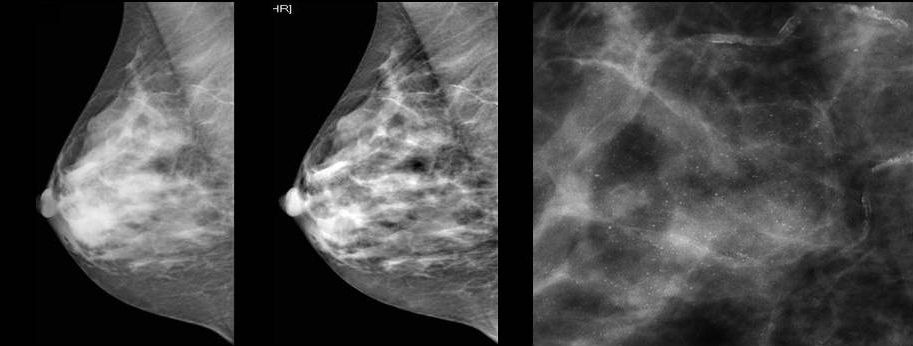

Для выявления злокачественных опухолей молочной железы существует определенный алгоритм диагностики, и его первичный элемент — маммографический скрининг. Чувствительность этого метода диагностики для опухолей от 2 мм до 5 мм составляет около 85%. Маммографическое исследование выполняют в двух проекциях.

Цифровая маммография РМЖ

Молодым женщинам с плотным строением молочной железы необходимо включение в программу наблюдения методов УЗИ и МРТ.